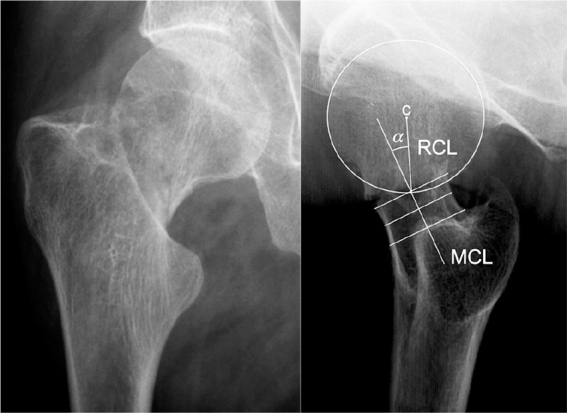

股骨颈骨折(FNFs)与所有年龄段的功能丧失和高死亡率相关。社会成本很高。治疗需要根据骨折类型、功能需求和患者的生理年龄量身定制。对于未移位的fnf和年轻患者移位的fnf,通常首选内固定。解剖复位是必要的,但轻微外翻是可以接受的。对于大多数移位的fnf,骨水泥半关节置换术是最好的选择。这篇教育性文章提出了fnf的治疗算法,并描述了推荐手术技术的证据基础。本综述不包括基础颈椎骨折、应力性骨折和病理性骨折。

Femoral neck fractures (FNFs) are associated with loss of function in all ages and excess mortality. The societal costs are high. Treatment needs to be tailored based on fracture type, functional demand, and physiological age of the patient. Internal fixation is often preferred for undisplaced FNFs and for displaced FNFs in young patients. Anatomical reduction is essential, but slight valgus is accepted. For a majority of those with displaced FNFs, a cemented hemiarthroplasty is the best alternative. This educational article suggests a treatment algorithm for FNFs and describes the evidence base for the recommended surgical techniques. Basicervical fractures, stress and pathological fractures are not included in this review.